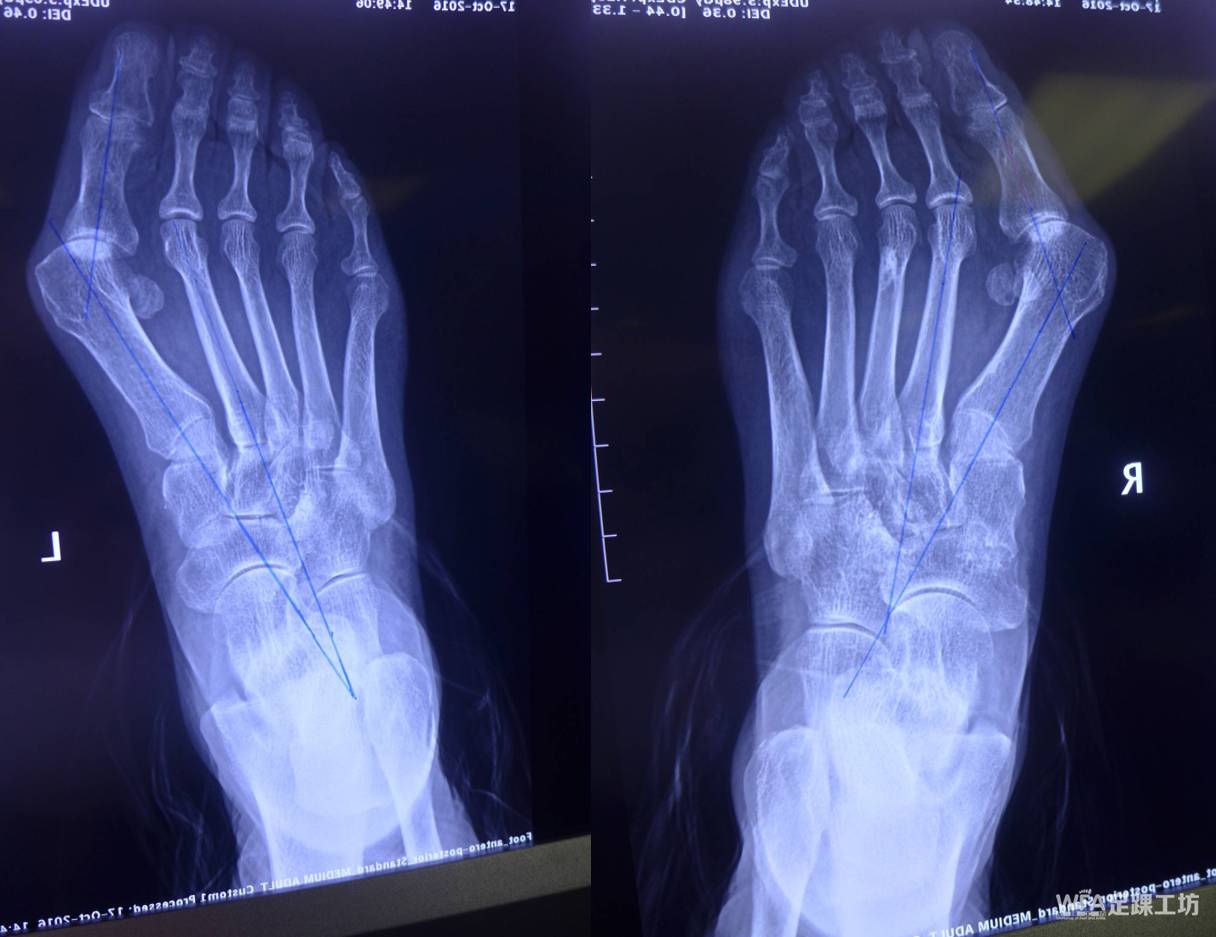

scarf联合akin截骨治疗中重度拇外翻畸形疗效分析

scarf截骨联合akin截骨治疗重度拇外翻

scarf截骨联合akin截骨可吸收螺钉或金属螺钉固定治疗中重度鳆外翻

akin截骨术在拇外翻手术中的应用学组专辑